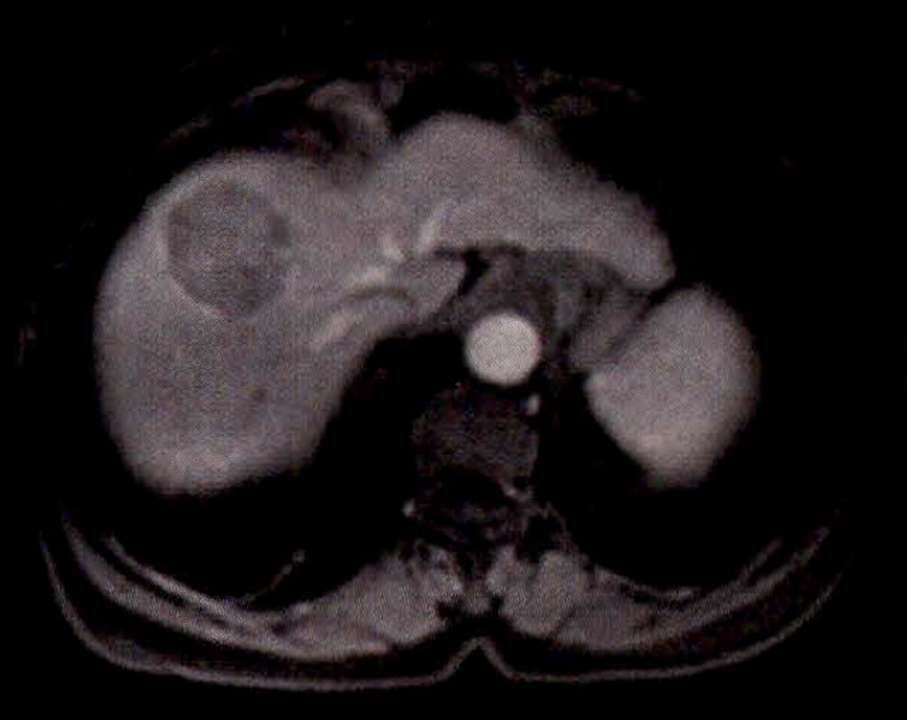

À l’examen clinique, vous retrouvez des signes d’insuffisance hépatocellulaire et d’hypertension portale associés à une hépatomégalie homogène à deux travers de doigts avec un bord inférieur tranchant. Le patient est marbré. Il existe une discrète ascite sans encéphalopathie associée. La palpation abdominale est indolore. Les constantes sont les suivantes : tension artérielle (TA) à 95/55 mmHg, pouls à 130/min, saturation en oxygène (SaO2) à 98 %, apyrétique.